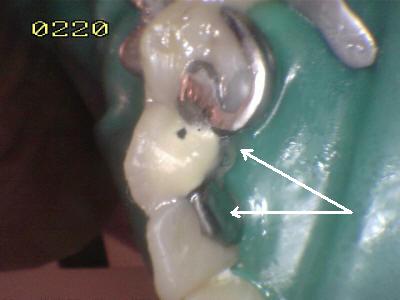

•  Aplicar el agente de enlace y fotopolimerizar como indica el fabricante. Preparar el cemento de curado dual y aplicarlos al puente sin dejar espacios que lo cubran y atrapar burbujas. Asentar el puente en los pilares y esperar hasta el endurecimiento inicial (al menos 2 minutos) Eliminar los excesos de cemento con explorador o cureta. (Flechas blancas)